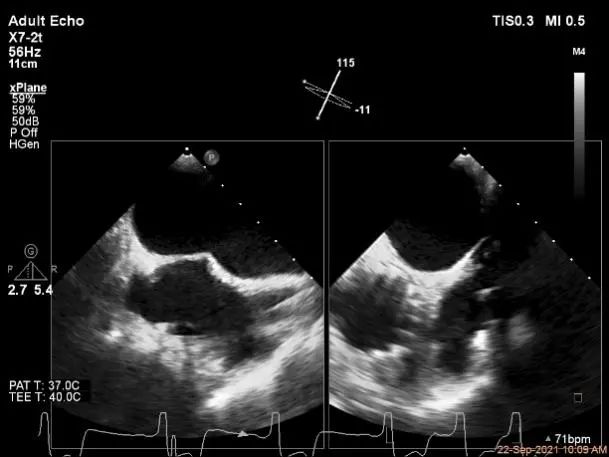

术中超声

3D:P1区脱垂并腱索断裂,Width:11.4mm

3D-color:重度MR,4级

麻醉状态下肺静脉血流频谱

MVA:7.8cm²,平均跨瓣压差:1mmHg

房间隔穿刺点选择

穿刺高度:4.08cm